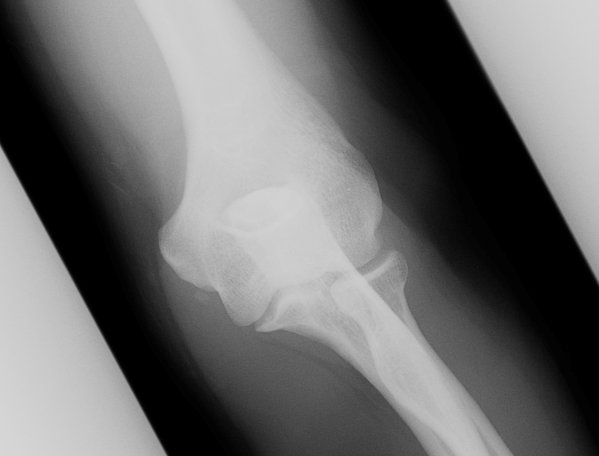

Return to Ulnar Collateral Ligament Injury